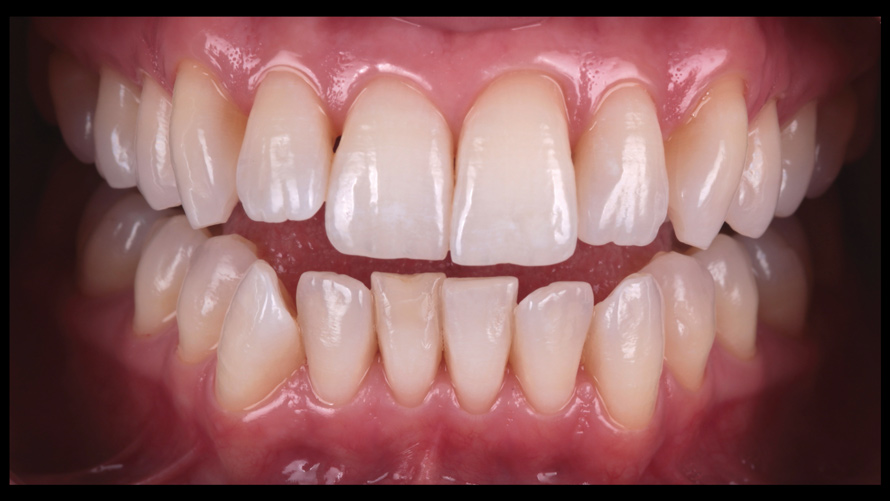

(9. through 11.) Preoperative esthetic case documentation using a smartphone and an EALS device.

Figure 9

Figure 10

Figure 11